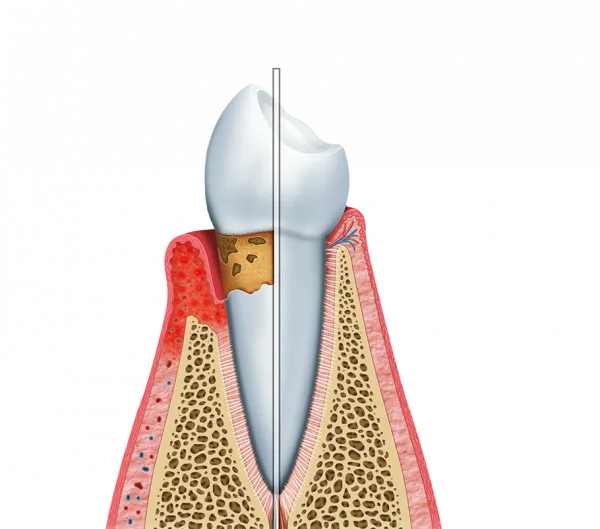

Este profissional, o periodontista, é treinado para diagnosticar e tratar problemas que afetam os tecidos de suporte dos dentes, possibilitando que a base da sua saúde bucal esteja firme e protegida.

A Periodontia é fundamental para prevenir doenças que, se negligenciadas, podem levar à perda dental.

Além do tratamento de quadros existentes, a consulta regular com um dentista especialista em gengiva atua na identificação precoce de inflamações, impedindo que problemas simples se tornem graves e exijam intervenções complexas no cotidiano.

O foco desse suporte especializado é possibilitar que as gengivas estejam rosadas, firmes e sem sangramentos.

Controle da Gengivite: Identificação e reversão imediata de inflamações superficiais;

Preservação Óssea: Tratamentos preventivos para evitar a periodontite e a perda de suporte dos dentes;